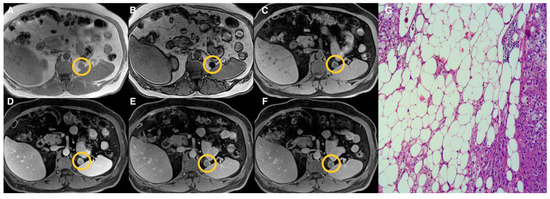

2.3. Image Analysis

3. Results